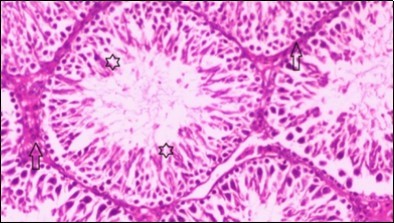

Histological examination of control rats' testis showed normal histological structure of the seminiferous tubules with an increase in the spermatogonia and other spermatocytes compared with the diabetic rats which showed an obvious decrease in the count of germinal cells generally and sloughing of germ cell in the lumen of seminiferous tubules in addition to absence of the mature sperms (Figure 3 and Figure 4). Rats tested of Fenugreek group and those treated with Glimepiride (Figure 5 and Figure 6) presented an increase in the number of spermatogenic cells and mature sperms with few focal necrotic cells. Whereas the combination therapy group showed normal histological structure of the seminiferous tubules with normal spermatogonia, presence of ledying cells and more mature of sperms (Figure 7). STZ reduced testosterone production, suggesting a decrease in the function of both Leydig (testosterone producing cell) and Sertoli (spermatogenesis) cells, which might be caused by a reduction in insulin secretion. These changes are probably due to increased Reactive Oxygen Species (ROS) production by accelerated Advanced Glycation End Products (AGE) formation 31 hexosamine and Protein Kinase C pathway. The administration of Fenugreek seeds to diabetic rats significantly decrease of sperm shape abnormality and improve the sperm count 32. Glimepiride reduced sperm abnormality and increased testis weights and sperm count by its antioxidant action 30. The potential protective efficacy of Fenugreek seed extract when added to Glimepiride was observed on reproductive systems.

Figure 7.Photomicrogragh of testis section of treated rat with combination of Fenugreek and Glimepiride showing nearly normal appearance of seminiferous tubules with organized spermatogenesis end with large number of spermatozoa (star). Note, Sertoli cells (arrows). (H&E) (40X).

Histological examination of pancreas of the control rats showed normal sized islets of pancreas (Ip) compared to the diabetic rats which showed markedly atrophic islets of pancreas (I.p.) (Figure 8 and Figure 9). Pancreas of in groups (3) and (4) rats showed mild atrophic islets of pancreas (I.p.) with inflammatory cellular infiltrate (Figure 10 and Figure 11). The pancreas of rats in group (5) showed nearly normal islets of pancreas (I.p.) with few inflammatory cellular infiltrate (I.c.) (Figure 12).